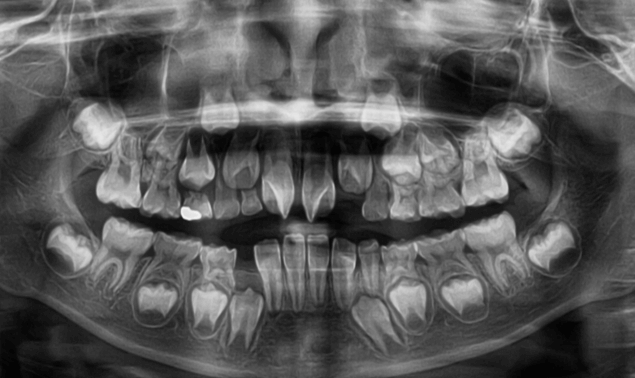

| 年齢・性別 | 8歳9ヶ月の女児 |

|---|---|

| 主訴 | 歯並びの乱れを気にされて来院された患者様です。将来的なスペース不足と歯のねじれ(翼状捻転)が懸念されました。 |

| 治療期間・回数 | 2年10ヶ月・19回 |

| 費用 | 430,000円(税別) |